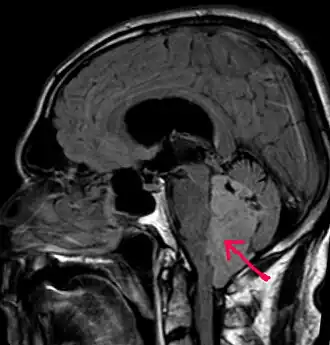

![]() МРТ больного с эпендимомой IV желудочка в Т1-взвешенном режиме. Опухоль отмечена стрелкой | |

В типичных случаях на МРТ эпендимомы видны в виде объёмных образований, которые заполняют, а иногда и полностью тампонируют полость IV желудочка и распространяются в большую затылочную цистерну или боковую цистерну моста. Солидная часть новообразования на Т1-взвешенных томограммах выглядит изо- или даже гипоинтенсивной и гиперинтенсивной на Т2-взвешенных томограммах[24].

Дифференциальная диагностика эпендимом с другими глиомами основывается в основном на их локализации и топографии, а не на различиях интенсивности сигнала или степени контрастного усиления[25]. Кистозный компонент имеет гипоинтенсивный сигнал на Т1-взвешенных МРТ и гиперинтенсивный по отношению к мозгу на изображениях, взвешенных по Т2. Гетерогенность структуры опухоли обусловлена наличием кист, петрификатов, опухолевой сосудистой сети. После введения контраста отмечается негомогенное усиление средней интенсивности[26]. Дифференциальную диагностику эпендимом боковых желудочков необходимо проводить с медуллобластомами и астроцитомами[23].